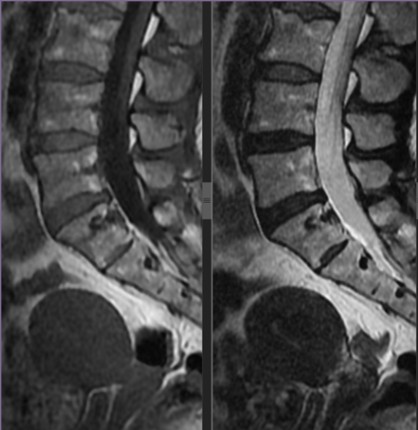

En estudios de extensión de tomografía toracoabdominal y resonancia de columna lumbosacra se observa una lesión osteolítica en cuerpo vertebral S1 (Fig 4 y 5.).

Figura 4. Tomografía toracoabdominal y resonancia de columna lumbosacra: Se observa una lesión osteolítica en el cuerpo vertebral S1.